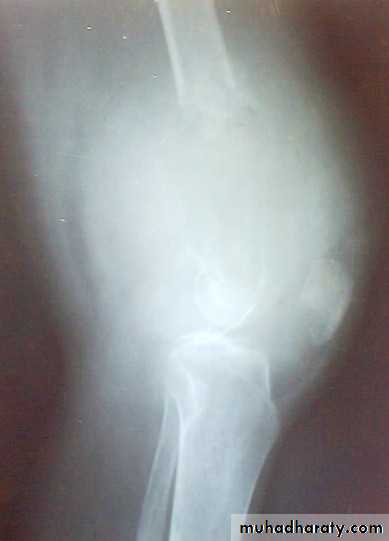

X-ray show eccentric osteolytic lesion in the end of long bone ,subchondral, trabeculated (soap bubble appearance). The cortex is thin, expanded or even perforated.

Patient presented by local pain and swelling or pathological fractures. Common site is the distal femur, proximal tibia, distal radius.